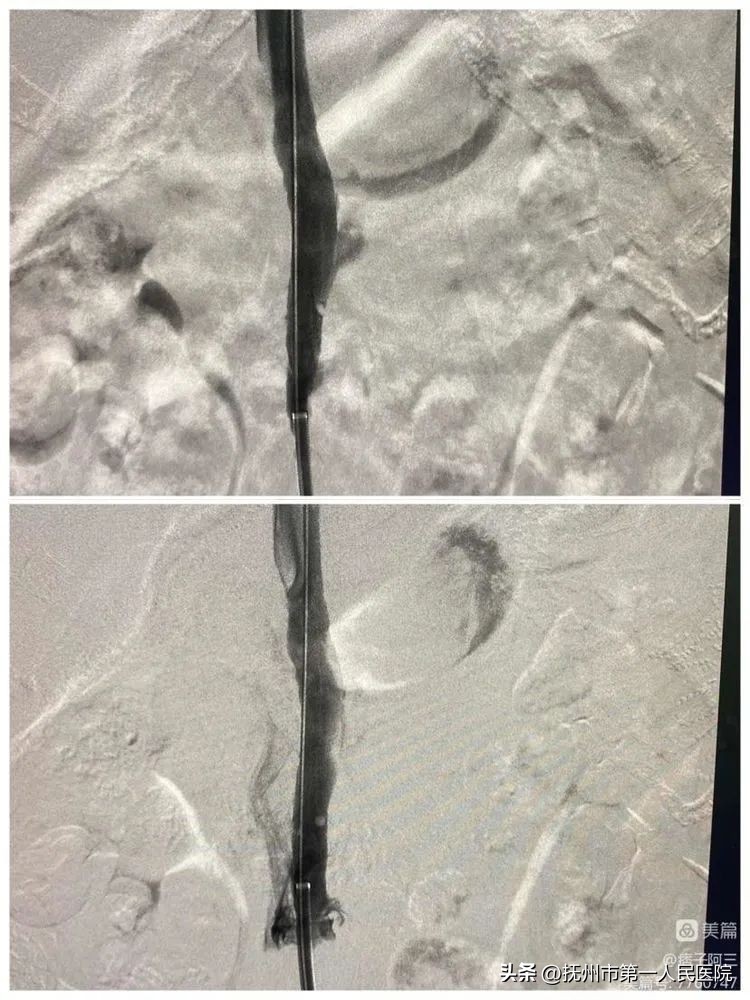

并给予F14球囊内扩

支架植入➕球囊内扩后再次造影及观察10分钟后造影下腔静脉显示均通畅、侧枝明显减少。手术结束